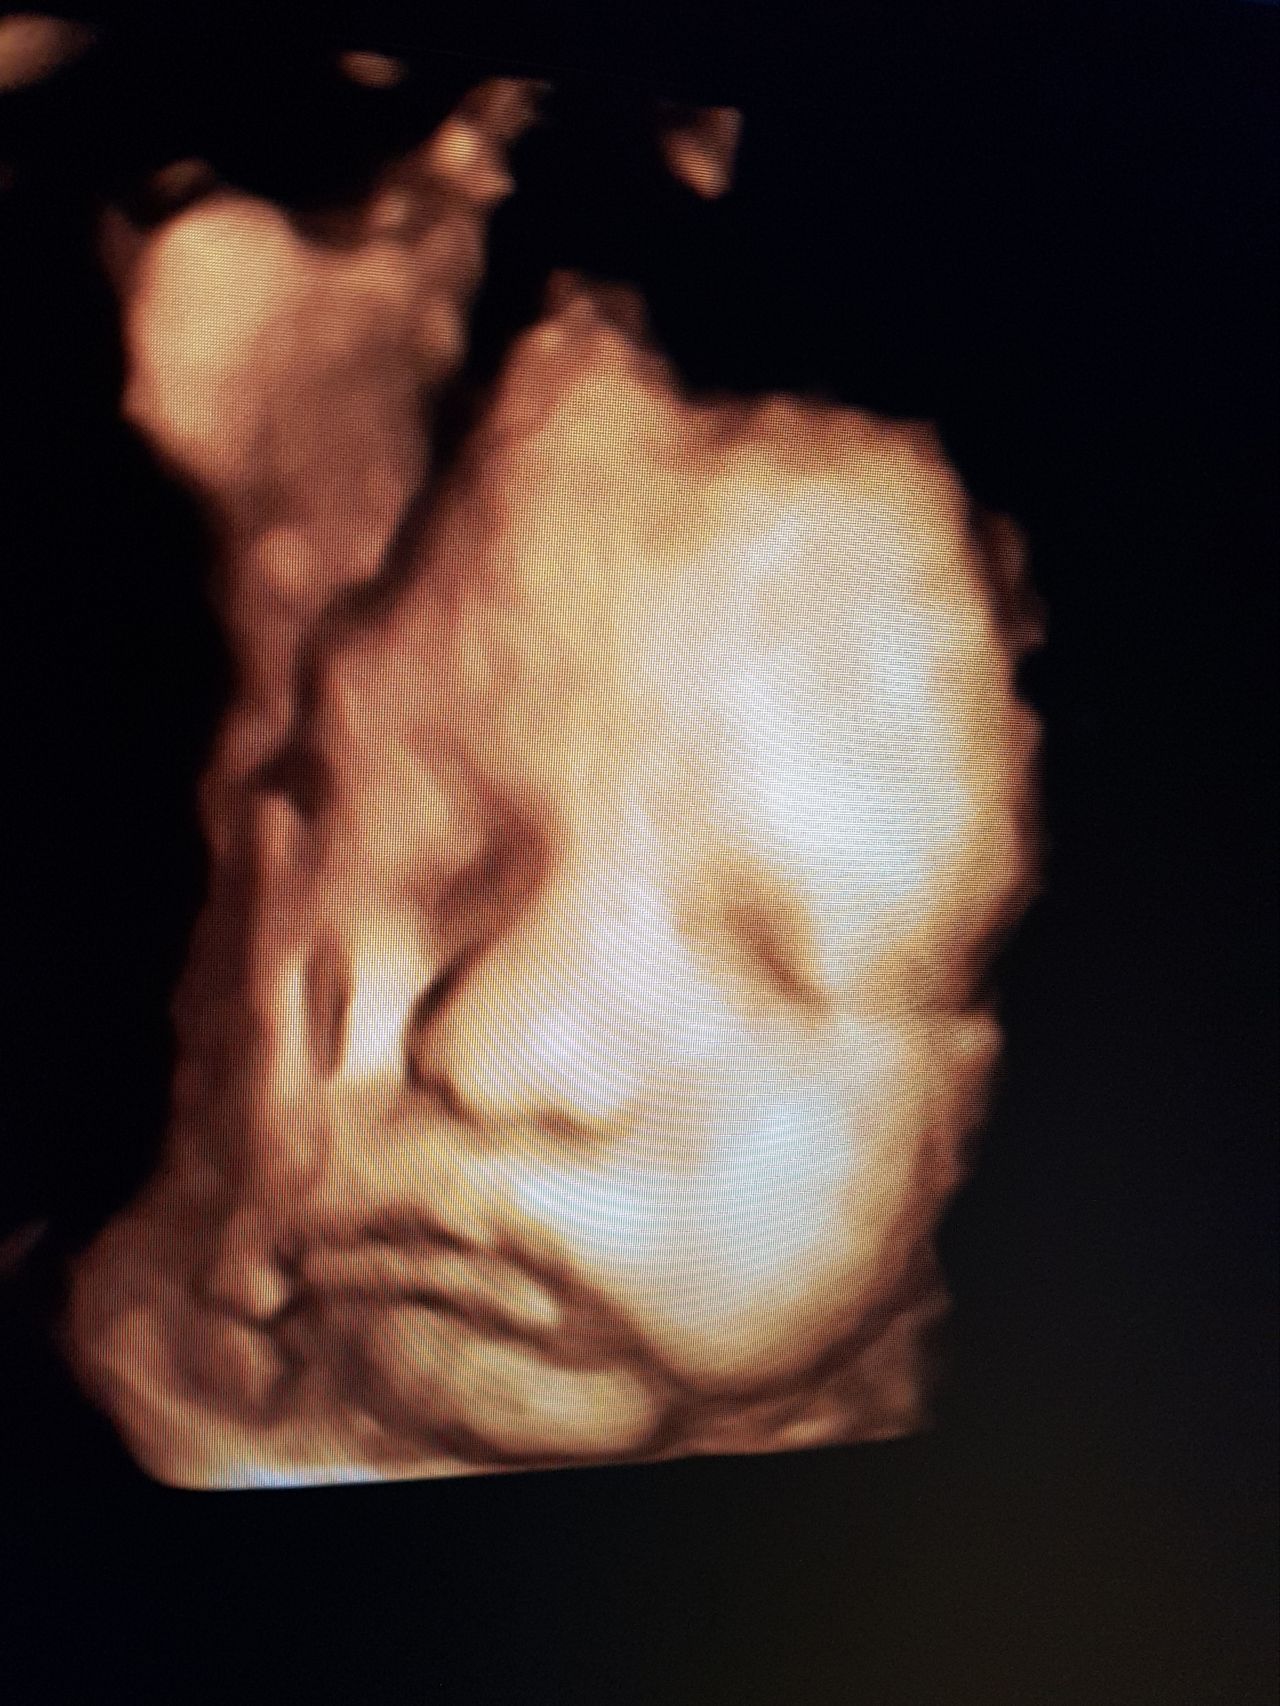

Foto e video